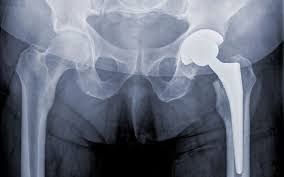

Hip pain can significantly affect daily life, mobility, and independence. For many patients in Gadchiroli, hip replacement surgery becomes necessary when medications, physiotherapy, or injections no longer relieve chronic pain. Hip replacement addresses arthritis, avascular necrosis, joint degeneration, or injury-related damage. Therefore, timely consultation with a skilled orthopedic specialist is essential to restore mobility, reduce pain, and improve overall quality of life.

Varunam Hospital in Gadchiroli provides comprehensive hip replacement services using modern surgical techniques. The hospital combines advanced operating theaters, precise imaging tools, and an experienced rehabilitation team to ensure the best patient outcomes. Under the leadership of Dr. Utsav Agrawal, Varunam Hospital emphasizes safety, comfort, and precision in every procedure. As a result, residents of Gadchiroli can access world-class hip replacement care without traveling to distant cities.

Varunam Hospital offers minimally invasive and robotic-assisted hip replacement for suitable patients. These techniques reduce tissue damage, minimize blood loss, and accelerate recovery. Moreover, robotic-assisted surgery allows precise implant placement, improving joint stability and long-term results. Under the expert supervision of Dr. Utsav Agrawal, patients in Gadchiroli experience safer procedures, smaller incisions, and faster rehabilitation without compromising surgical effectiveness.